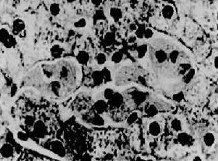

本病的基本生化缺陷是缺乏一種溶酶體水解酶,即α-岩藻糖苷酶,該基因定位在2q24~q32。病人的腦肝、腎、肺、尿內都有酶缺乏。腦肝等組織的沉積物是一種含有岩藻糖的糖脂(以岩藻糖為終末部分的四己糖基及五己糖基神經醯胺)特別是腦內最為明顯是本病的發病機制。本病分幼兒型和成人型幼兒型的病理改變為肝細胞內有特徵性細胞質包涵體及許多直徑為0.5~5µm的空泡,空泡外包有一層膜,一些空泡內含有透明的碳水化合物,必須用過碘酸染色才能顯示出空泡內容物。還有一些空泡內充以親水性圓形結構,這種結構是由複合性脂質特異的板層所組成。細胞質包涵體也可見於庫普弗細胞、組織細胞、巨噬細胞腎小體上皮細胞、膽管上皮細胞、內皮細胞和心肌細胞。大多數細胞含有許多透明空泡,也可見親水性緻密包涵體和成層結構物質沉積。在腦組織內白質顯示有大量巨噬細胞和髓磷脂明顯損失,血管周圍間隙存在顆粒狀脂質。在灰質內有神經元喪失,殘存的神經元均含有外面包有一層膜的透明空泡,直徑為0.8~2.4µm其內含有小顆粒網狀及少量平行的成層結構。星形細胞、少突神經細胞及毛細血管內皮細胞,也含有透明空泡或緻密親水網狀物質在組織化學上,包涵體呈PAS染色弱陽性,鹼性染色無異染性。